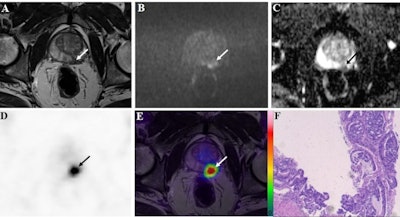

The researchers looked at imaging of 29 consecutive male patients with suspected prostate cancer who underwent preoperative whole-body F-18 PSMA-1007-PET/MRI scans (3-tesla Biograph mMR, Siemens Healthineers), and subsequent targeted biopsy for suspected cancerous lesions (n = 48) between June 2019 and June 2021.

Two nuclear medicine physicians with more than five years of experience each interpreted the images. First, they assessed all bpMRI images of each suspected lesion. Next, they studied the PET images with the MRI images as anatomical background. Finally, they reviewed all lesions with access to the individual evaluations of PET and bpMRI images to arrive at combined PET/MRI findings.

In addition, the group studied whether the PET/MRI and bpMRI results correlated with International Society of Urological Pathology (ISUP) grades, an effective new clinical cancer severity grading system. These correlations were based on receiver operating characteristic (ROC) curves of optimal standardized uptake values (SUVmax) for PET/MRI and apparent diffusion coefficients (ADC) for bpMRI.

Out of the 48 suspected prostate cancer lesions in 29 patients, 38 were identified with biopsies as clinically significant prostate cancer, and 10 were noncancerous lesions. Against these pathological results, F-18 PSMA-1007 PET/MRI demonstrated much greater diagnostic accuracy (area under the curve [AUC]), sensitivity, specificity, positive predictive value (PPV), and negative predictive value (NPV) than bpMRI, the researchers found.

In addition, a high SUVmax of F-18 PSMA-1007 radiotracer detected on PET/MRI may indicate a lesion with a high ISUP grade, the authors wrote. The semiquantitative parameters of SUVmax demonstrated a higher AUC (0.874) than that of ADC (0.776) for detecting prostate cancer.